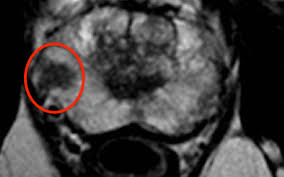

These results support findings in prior studies showing that mri … Because the mri showed which areas of the prostate were most suspicious for cancer, fewer than the standard 12 biopsy samples were needed. This trial focused on the accuracy of mri for staging prostate cancer in men with clinically localized disease and who had radical prostatectomy. High resolution mr images especially with the use of endorectal coil can show with high accuracy whether the tumor is confined to prostate gland or there is involvement of prostate capsule and extra capsular extension that is considered the t component of tnm staging … There are a few different systems used for staging prostate cancer. Mri scan an mri (magnetic resonance imaging) scan uses magnets to create a detailed picture of your prostate and the surrounding tissues. 22.01.2019 · an earlier established role for prostate mri had been local staging prior to treatment. Prostate cancer staging takes into account tnm (primary site, nodal and distant metastases), pretreatment psa and histological grading.

High resolution mr images especially with the use of endorectal coil can show with high accuracy whether the tumor is confined to prostate gland or there is involvement of prostate capsule and extra capsular extension that is considered the t component of tnm staging … Prostate mri in general and prostate mr spectroscopy (mrsi) specifically. Mri scan an mri (magnetic resonance imaging) scan uses magnets to create a detailed picture of your prostate and the surrounding tissues. These results support findings in prior studies showing that mri … There are a few different systems used for staging prostate cancer. Because the mri showed which areas of the prostate were most suspicious for cancer, fewer than the standard 12 biopsy samples were needed. 22.01.2019 · an earlier established role for prostate mri had been local staging prior to treatment. A simplified number staging system is described below. Mri scans can show if the cancer has spread outside the prostate into the seminal vesicles or other nearby structures. If prostate cancer has been found, mri can be done to help determine the extent (stage) of the cancer. The tumour is too small to be felt when a doctor does a rectal examination or to be seen on a scan. Also, 37% of the men who had a completely normal mri were able to avoid biopsy. 05.12.2013 · imaging techniques play a significant role in staging of prostate cancer and mri is the most accurate imaging modality used for prostate cancer staging.